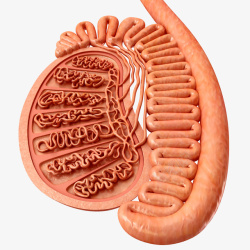

生殖横断面立体插画

人体器官构造